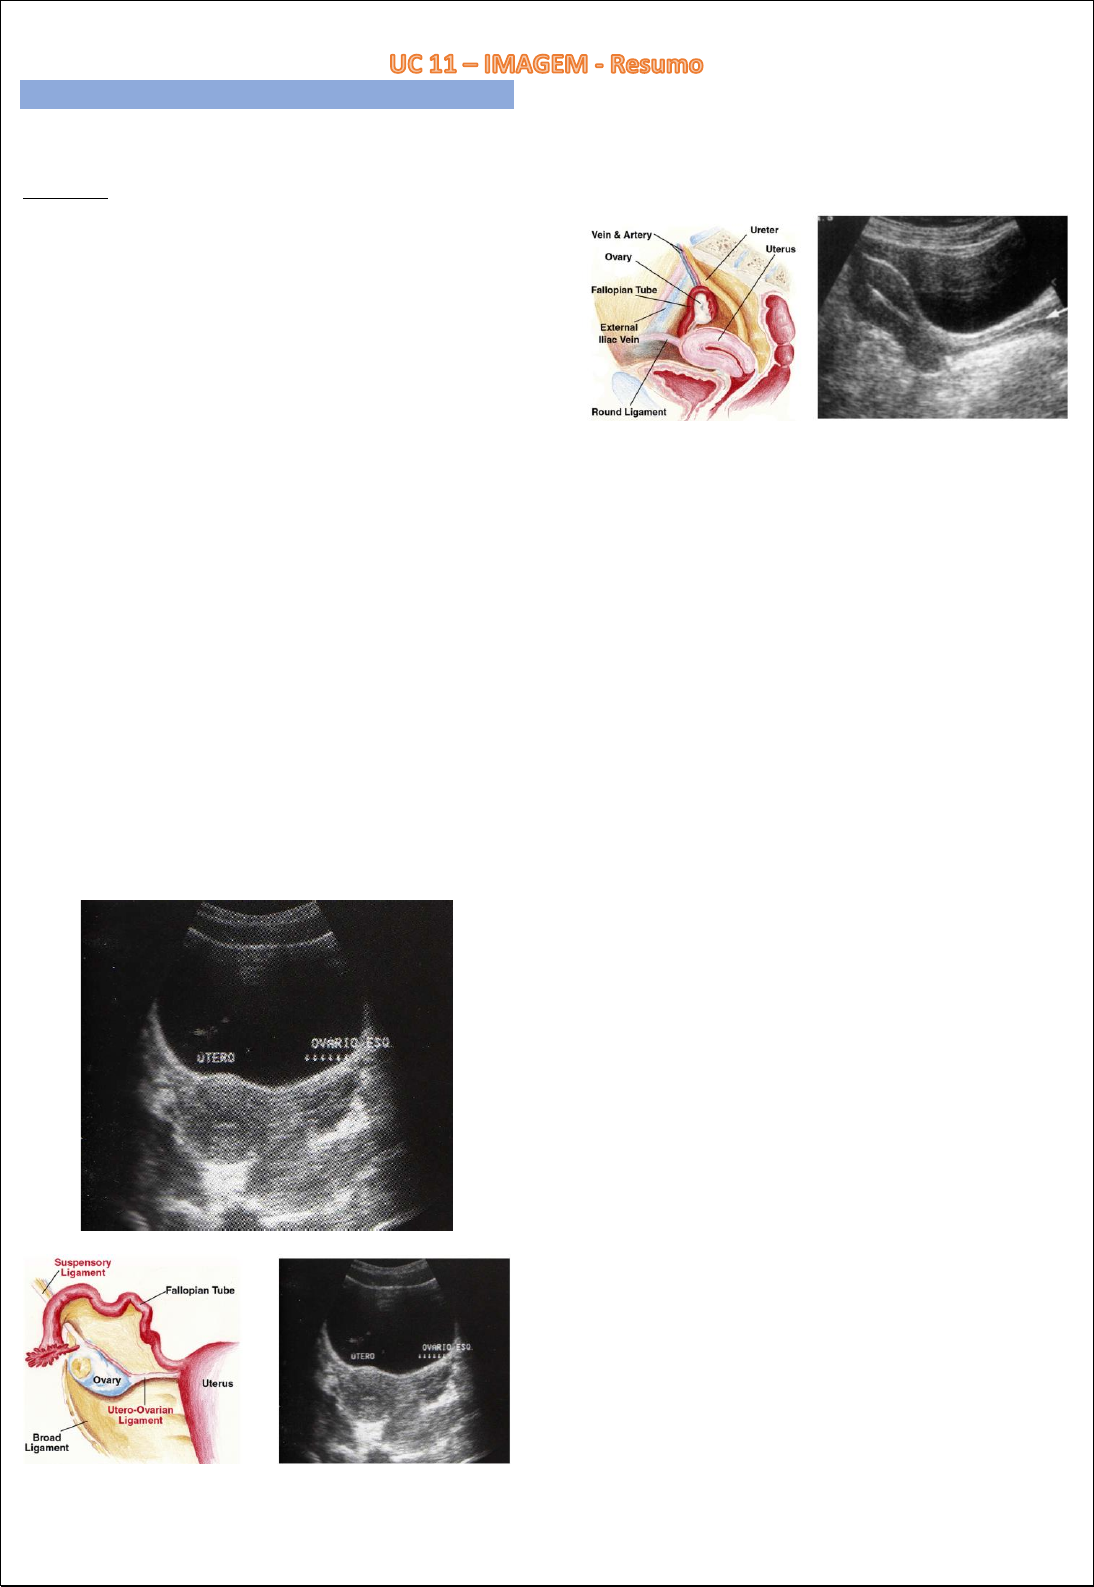

Slideshow endométrio heterogêneo o que significa

Endométrio heterogêneo